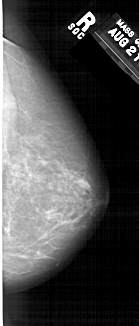

A_1370_1.RIGHT_MLO

RIGHT_MLO LINES 6856 PIXELS_PER_LINE 2911 BITS_PER_PIXEL 12 RESOLUTION 43.5 NON_OVERLAY

FILE: A_1370_1.LEFT_CC.OVERLAY

TOTAL_ABNORMALITIES 1

ABNORMALITY 1

LESION_TYPE MASS SHAPE IRREGULAR MARGINS ILL_DEFINED

ASSESSMENT 4

SUBTLETY 3

PATHOLOGY BENIGN

TOTAL_OUTLINES 1

BOUNDARY